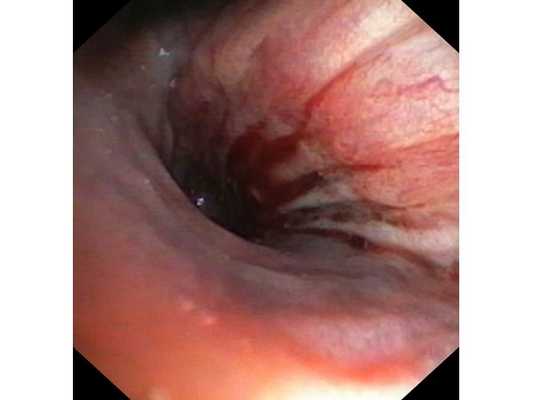

Первым этапом пациенту была проведена фибробронхоскопия, по данным которой выявлено, что устье нижнедолевого бронха слева сужено за счёт подслизистого и перибронхиального распространения опухоли.

Выполнена многократная биопсия из устья нижнедолевого бронха слева. По данным гистологического исследования материала эндоскопической биопсии верифицирован диагноз немелкоклеточного рака лёгкого.

- Бронхоскопия, биопсия. Бронхоскопия — это визуальное исследование бронхов, для которого используется миниатюрная видеокамера с подсветкой — бронхоскоп. Этот прибор вводится через нос, опускается в трахею и далее в бронх. С помощью бронхоскопа можно изучить опухоль, а также взять образец ткани из нее. Этот метод называется биопсией. После забора образца ткани он подвергается гистологическому исследованию. Гистология не только помогает отличить доброкачественное новообразование от злокачественной опухоли и поставить однозначный диагноз, но также оценить степень злокачественности раковых клеток, а значит, оценить риск рецидива опухоли после операции. Эта информация очень важна для определения необходимых объемов хирургического вмешательства и удаления тканей. Забор образца опухолевой ткани может быть выполнен посредством тонкоигольной биопсии, с помощью тонкой полой иглы, которая вводится в опухоль чрескожно под контролем УЗИ.